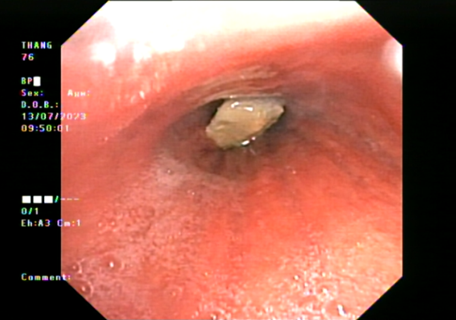

Bệnh nhân được nhập viện điều trị kháng sinh và chống viêm tích cực, ổn định tình trạng nhiễm trùng, sau đó thực hiện Nội soi phế quản ống mềm gắp dị vật phế quản do Bác sĩ CKI Nguyễn Văn Hùng và ĐDV Đào Văn Thanh thực hiện. Phát hiện dị vật là một mảnh xương nằm tại Phế quản trung gian phổi Phải, niêm mạc phế quản xung quanh phù nề, thâm nhiễm và che phủ một phần dị vật, xung huyết, dễ chảy máu, tổ chức hạt cùng dị vật bít kín gần hoàn toàn lỗ phế quản. Ekip nội soi đã tiến hành gắp dị vật bằng kìm gặp dị vật, kết hợp cầm máu tại chỗ và lấy ra được dị vật là một mảnh xương có kích thước 14x14x3 mm.

Hình 2: Hình ảnh dị vật qua nội soi